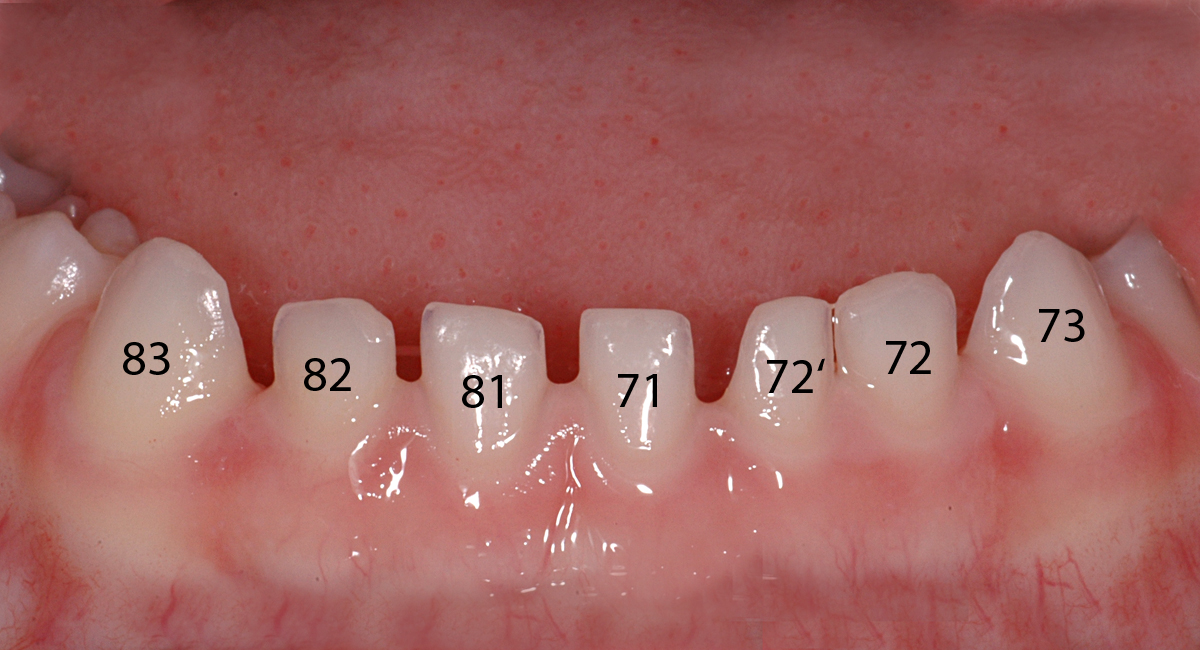

In diesem Fall eines 3-jährigen Knaben ist ein überzähliger Milchzahn in der Unterkiefer-Front zu sehen. Er ist im zweiten Bild mit 72' bezeichnet. Hierbei handelt es sich um eine Doppelanlage des seitlichen Schneidezahnes unten links.

Diese Situation erfordert keinerlei EIngreifen oder andere Massnahmen. Der Zahn kann vorerst einfach so belassen werden und in der Regel behebt sich dieses «Problem» mit dem Zahnwechsel von selbst.

Ansicht mit Zahnbezeichnungen